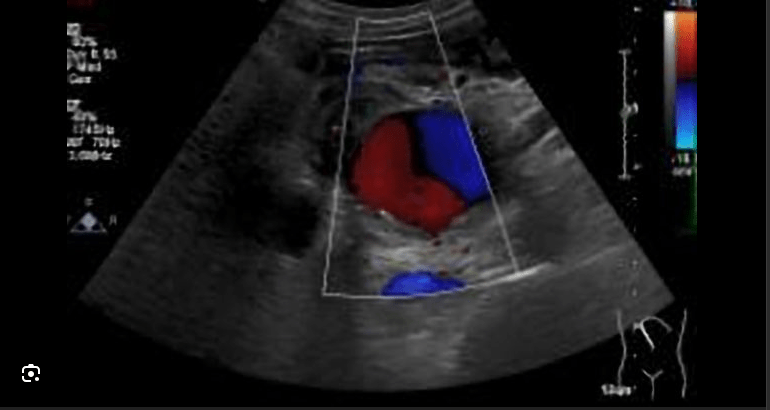

Ying-yang sign indicates this pathology.

What is aneurysm or pseudoaneurysm?